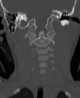

Asymmetric atlantoaxial joint

Torticollis, also known as wry neck, is a dystonic condition defined by an abnormal, asymmetrical head or neck position, which may be due to a variety of causes. The term torticollis is derived from the Latin words tortus for twisted and collum for neck.The most common case has no obvious cause, and the pain and difficulty with turning the head usually goes away after a few days, even without treatment. [Source: Wikipedia ]